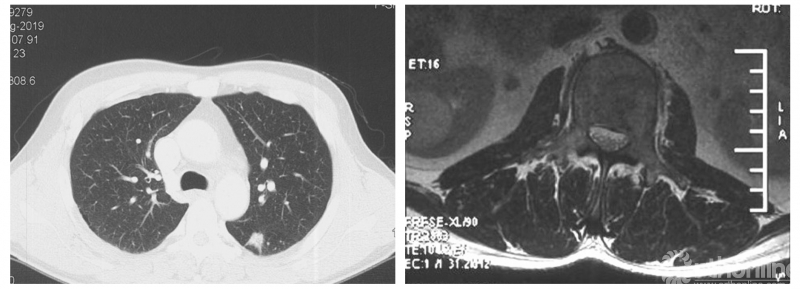

影像学资料

PVP治疗

患者房某,男性、51岁。主因“腰痛3个月”入院,既往外院诊断“周围型肺腺癌”,全身检查提示多发骨转移。

经Spine Oncology Study Group(SOSG)评估硬膜外脊髓压迫(ESCC)为Grade 1a型,轻度脊髓压迫;脊柱机械稳定性评估(SINS)7分,中度不稳。修正Tokuhashi评分(RTS)6分,预计生存<6个月,建议姑息性手术及保守治疗;结合Tomita评分系统6分,故行姑息性手术短期控制。